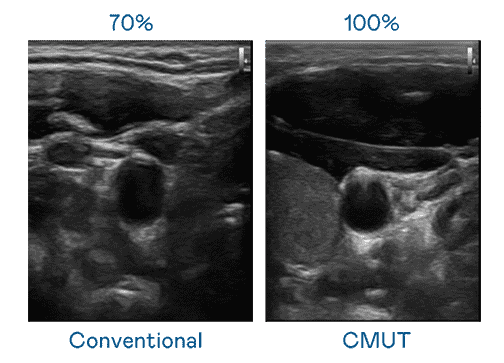

CMUT 技术是一种用电容式微机电元件来产生超音波讯号的技术。。。。与传统 PZT 压电式技术相比,,,CMUT 频宽增加 30%,,,更宽频的超音波讯号让影像解析度大幅提升,,是实现高影像品质医疗超音波扫描、、、、促进精准医疗发展的关键技术。。。。

大频宽带来超清晰影像

超音波影像的解析度高低,,,首先取决于探头能发出的讯号频宽。。赏金国际 CMUT 可提供高清晰的超音波讯号,,,提供高频宽、、、高灵敏度、、影像纹理细节更高的超音波影像,,,协助医护人员缩短影像判读时间及利用精准的医疗影像进行诊断。。。